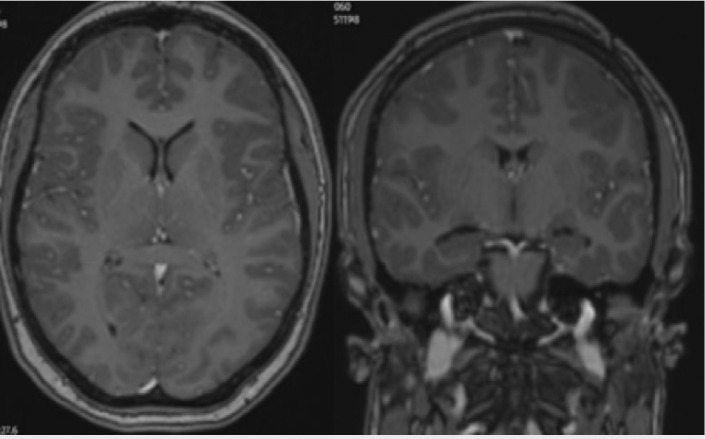

Pachymeningitis in a pediatric case of IgG4-related disease successfully treated with mycophenolate mofetil.

Abstract Image